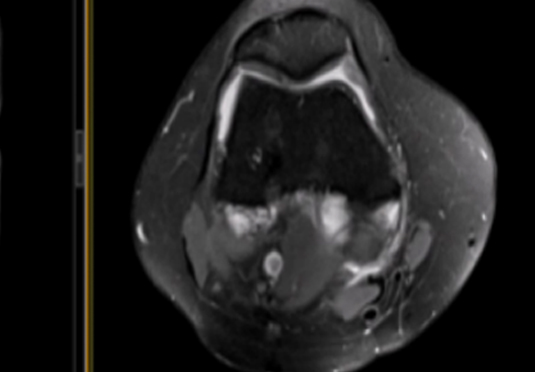

• 微創技術rf射頻融入術

合用于微創射頻熱融化術醫治患者,引進權勢巨子醫療集體幫助引流。

微創射頻融化術